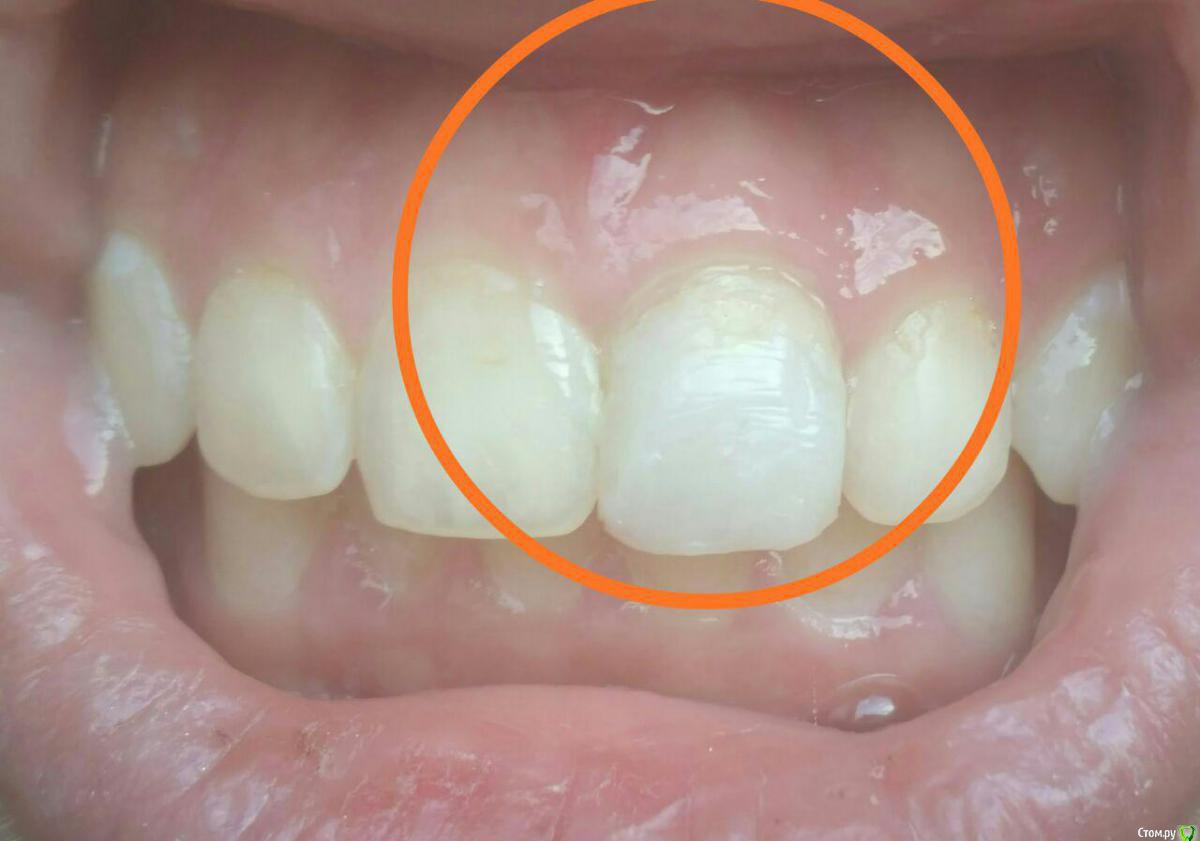

golneva Опубликовано 24 апреля, 2018 Поделиться Опубликовано 24 апреля, 2018 (изменено) Добрый день. Около трех месяцев назад не вписалась в дверной проем с утра и сломала передний верхний зуб. Пол зуба просто откололась. Сразу же обратилась к врачу (врач из очень опытных, наверное больше 30 лет стажа, посоветовали блин). Удалил нерв, залепил "лекарство" через три дня запломбировал канал. Из вариантов лечения предложил только одеть металлокерамику и все. Согласилась потому что никогда не сталкивалась с протезированием, думала что лет до 35 все будет ок, мне 22 года, только 2 пломбы в зубах. После установку вкладки ( хотя это трудно назвать вкладкой) зуб начал болеть, болел очень сильно, врач выписал антибиотики, очень сильный препарат с кучей побочных эффектов, которые я ощутила неподетски, зуб стал болеть чуть меньше и он решил что можно обточить, наколол анестезию такую что в глазах двоилось, но во время обточки он не использовал ни воду, ни десну не защитил и больно было так как будто он меня по живому режет. Прописал другой антибиотик и хлористый кальций, через неделю закончил с обтачиванием, зуб практически не болел. После обтачивания боль слегка усилилась, но когда нужно было одеть коронку он уже почти не болел. Коронка не подошла идеально и врач снова решил обтачивать зуб, и снова было дико больно даже с сильной анестезией. Я говорила что мне больно, врач говорил что я ему вру. Когда я уже не могла терпеть он просто вручил мне в руку коронку и выпроводил. Вся эта канитель длилась чуть больше месяца. В тот же день я пошла к другому врачу, мне сразу сделали снимок где видно что у мня не допломбирован канал, вкладка это просто кусок железки, и между вкладкой и пломбой в канале пустота. На следующий день сделала КТ по совету доктора, он думал что треснул корень. Корень был целым. Доктор достал вкладку (доставал 3 часа), неделю я ходила с "лекарством" с йодом, потом дней 10 с кальцием, канал запломбировали недели три назад. Перед пломбирование зуб не болел совсем. Хожу с временной коронкой, он не болел ни при накусывании, ни при постукивании. Запломбировали хорошо и корень целый. После пломбировки зуб был чувствительным, через неделю был назначен прием чтобы сделать слепок для вкладки, но зуб побаливал и ничего не делали. Доктор сказал подождать надо. Сейчас после пломбирования (прошло уже 3 недели) зуб побаливает при накусывании, при постукивании, даже если прижать его губой он побаливает. Но боль странная, не ноющая как была раньше, а похоже на укол. Ка будто сильнейшая чувствительность, эту ощущение в последние сутки все время, как будто ем лед. если оценить по десяти бальной шкале то это где-то от единицы до трех.может кто-то сталкивался с таким, я не знаю что делать. Есть снимки только сразу после удаления нерва и через месяц после этого. Срезы КТ прилагаю, но только сбоку. Остальные снимки в клинике. Что это просто чувствительность, авитаминоз, фантомные боли??SLX+002.BMP Изменено 24 апреля, 2018 пользователем golneva Ссылка на комментарий

red_butler Опубликовано 25 апреля, 2018 Поделиться Опубликовано 25 апреля, 2018 сделать еще одно КТ? даи фото во рту Ссылка на комментарий

golneva Опубликовано 25 апреля, 2018 Автор Поделиться Опубликовано 25 апреля, 2018 меня смущает темнота на верхушке корня левой единички. Или так и должно быть? Спасибо всем участникам за ответы. Ссылка на комментарий